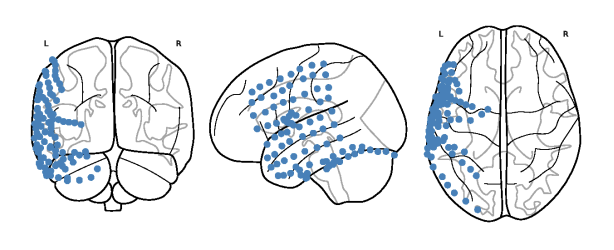

1. Neuroscience

ecog_map.png

Decoding Happiness from Neural and Video Recordings for Better Insight Into Emotional Processing in the Brain

Emil Azadian, Gautham Velchuru, Nancy Wang, and 3 more authors

In 2021 43rd Annual International Conference of the IEEE Engineering in Medicine & Biology Society (EMBC), 2021